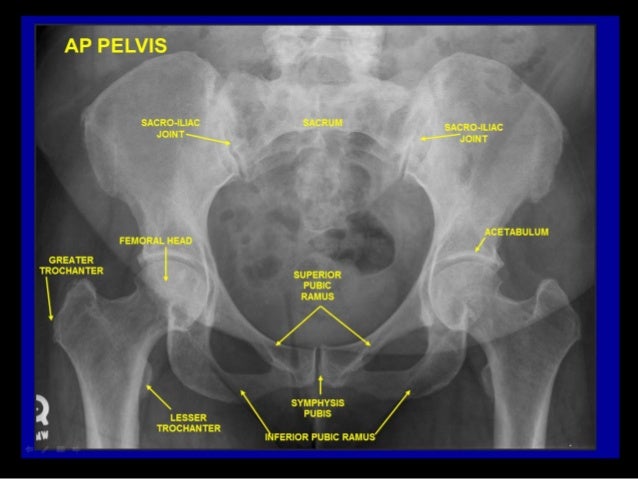

Radiographic Anatomy Of Abd And Pelvis R A

pelvis radiographic ct abdomen